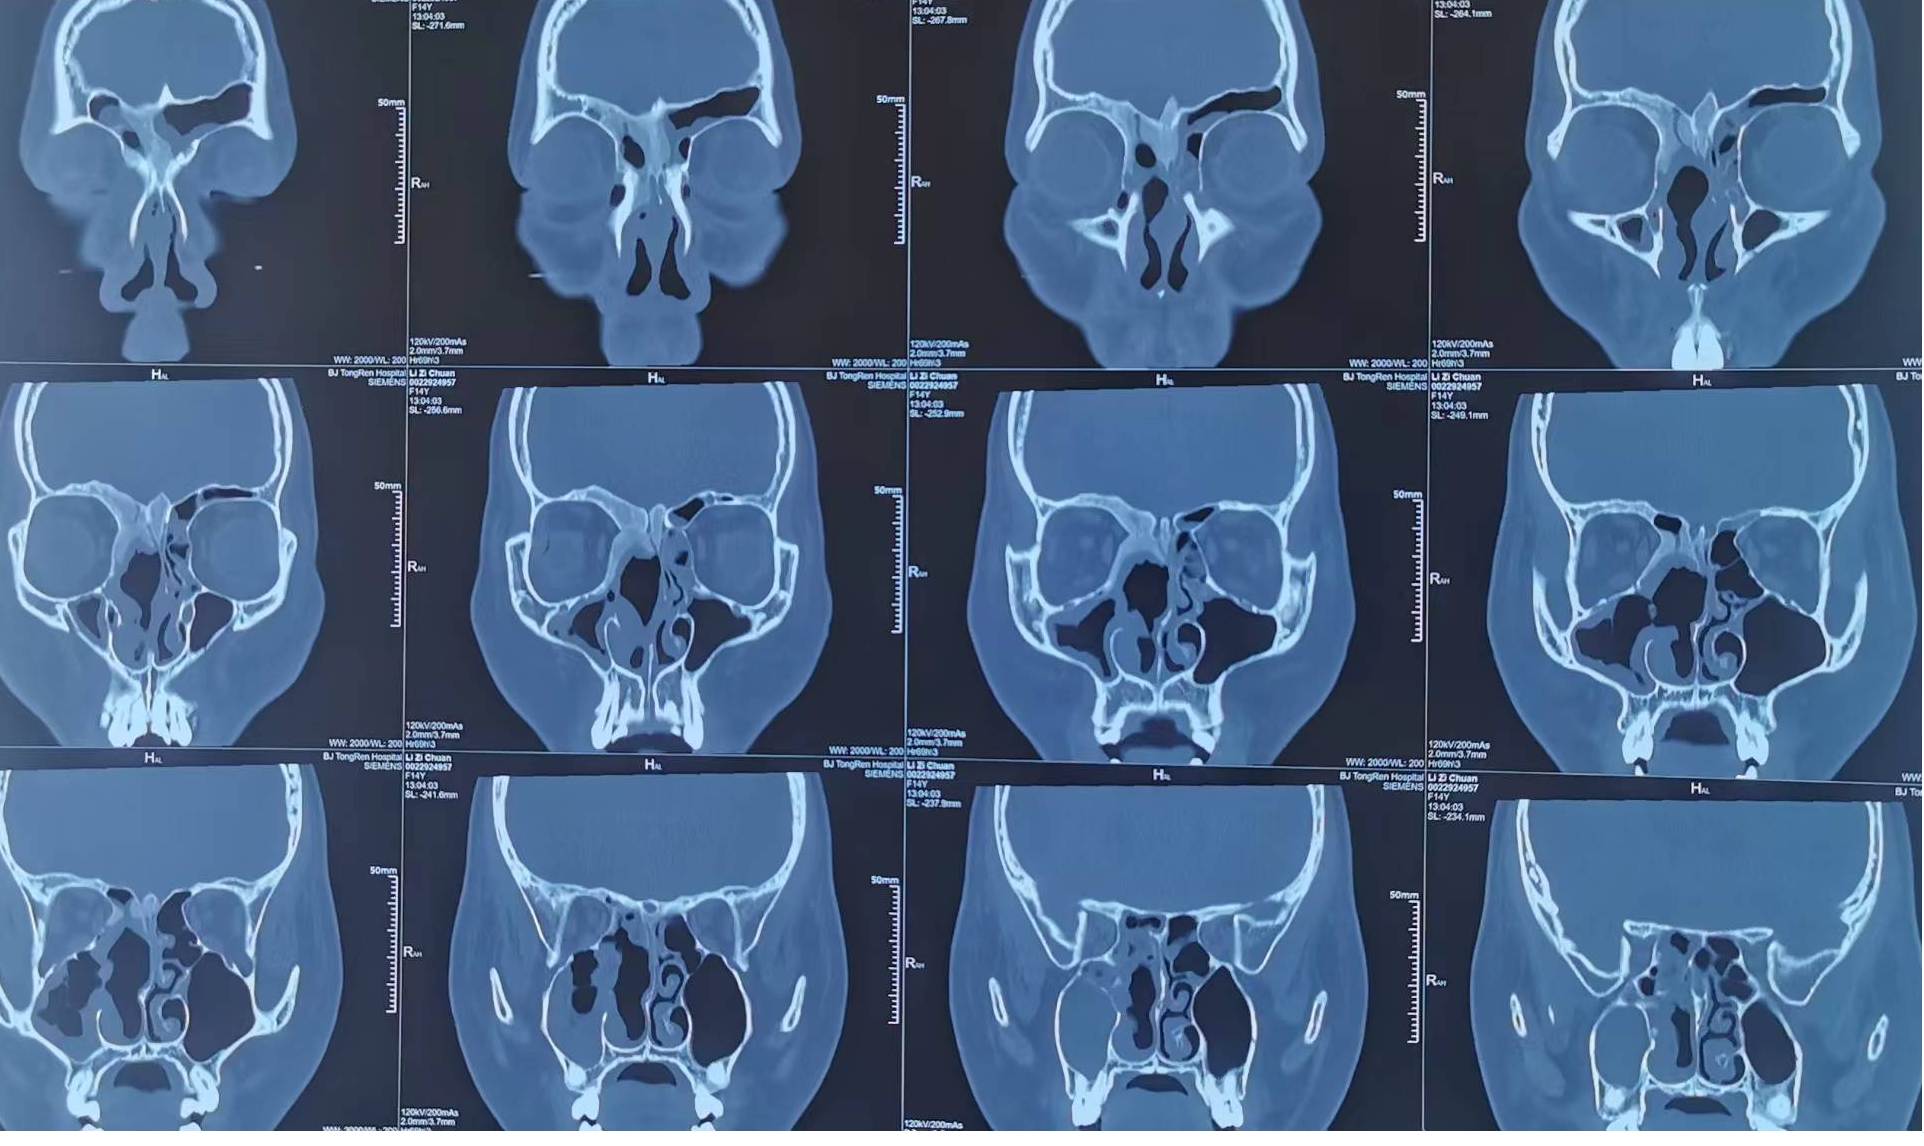

鼻堵,頭痛就醫(yī),CT發(fā)現(xiàn)累及眶骨、雞冠鼻甲的骨纖維異常增殖癥。經(jīng)鼻內(nèi)窺鏡手術(shù),切除增生的中鼻甲,鼻堵及頭痛明顯緩解。建議此病人定期復(fù)查CT,觀察骨纖生長情況,如累及視神經(jīng)管,定期復(fù)查視力。